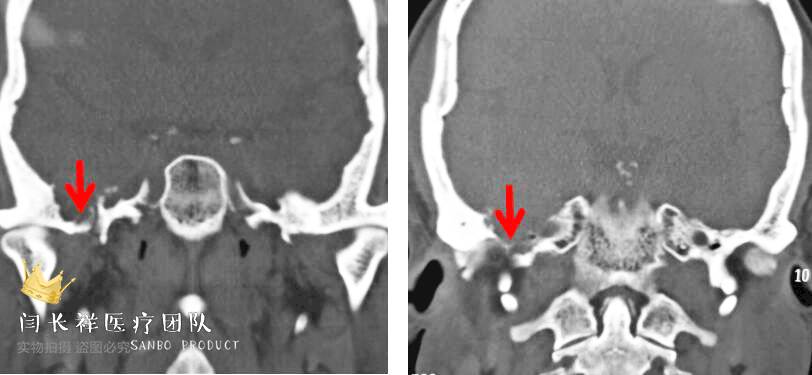

术前冠位CT示右侧中颅窝、颞下窝、翼腭窝占位,病灶呈稍高密度。

术前冠位CT骨窗像示右侧中颅窝底骨质被肿瘤侵蚀破坏。